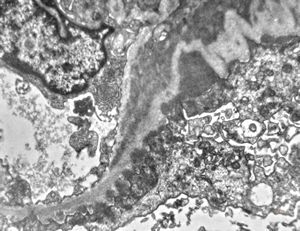

M,22y. | type II membranoproliferative glomerulonephritis